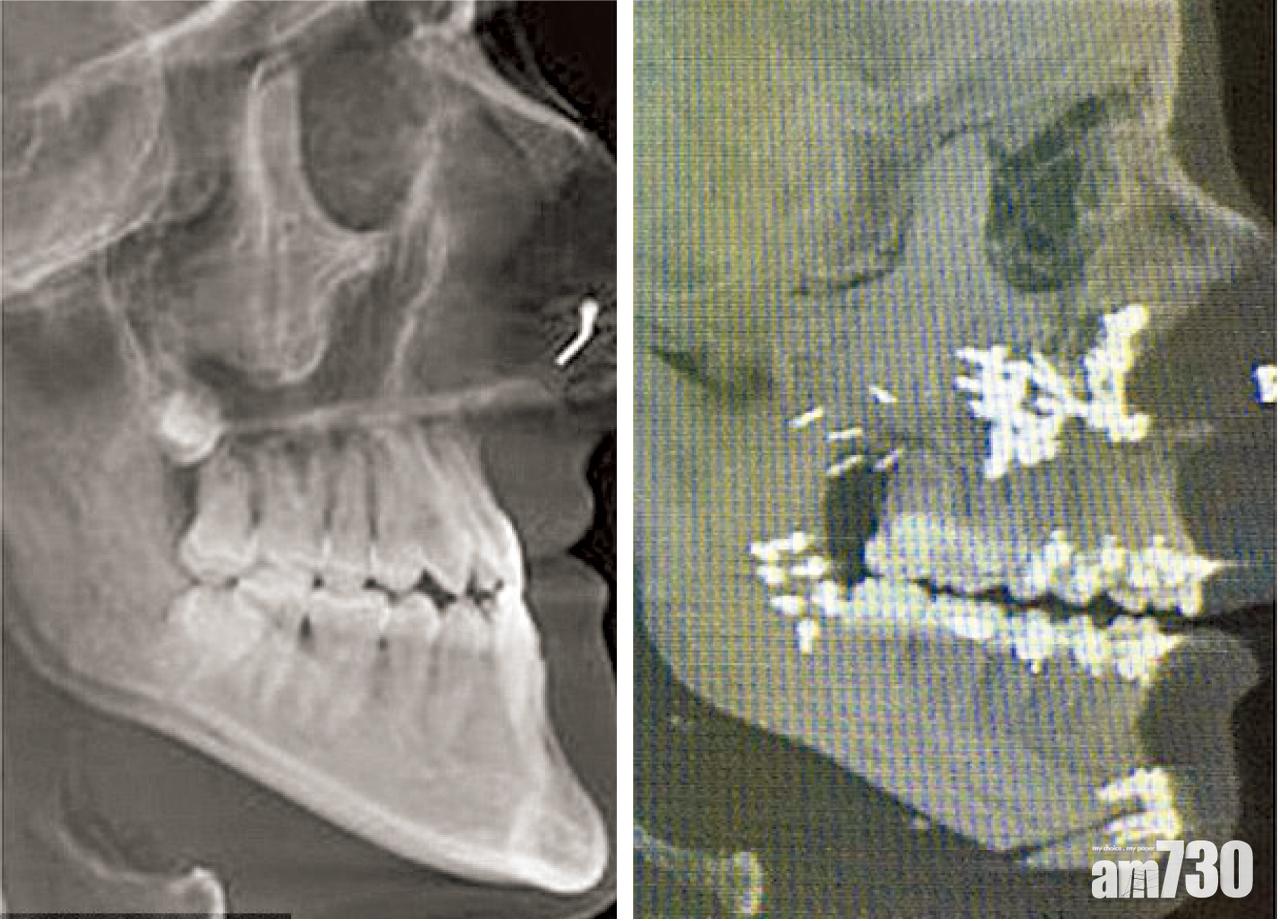

直至4個月前,她接受雙顎手術:割出上下顎修整顎骨,再以36枚螺絲釘及下巴碎骨鑲補裝回原位。如今,她除「報復式變靚」,有生以來也首度正常咀嚼享受食物!